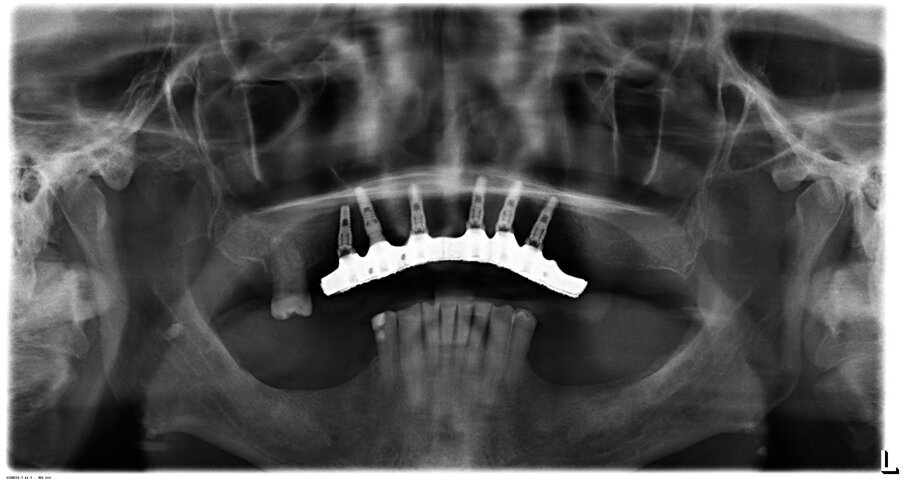

Condividiamo con il paziente la scelta terapeutica di riabilitazione implantoprotesica che nella 1 fase consisterà in riabilitazione occlusale mediante l’applicazione di protesi provvisoria, e successivamente inserimento di 6 impianti nel mascellare a carico ritardato e seguente applicazione di barra per una overdenture. Il paziente necessita di una riabilitazione oro-implantare protesica, in quanto sia all’esame obiettivo che all’esame radiografico presenta una ridotta dimensione verticale che negli anni ha portato alla distruzione degli elementi inferiori dal 34 al 44, e persistenza di 11, 13, 17, 25 che presentano abrasioni e abfrazioni sulla superficie coronale (Fig. 2). Dopo aver condiviso con il paziente le problematiche terapeutiche dovute anche alla sua condizione di patologia sistemica, si decise, di procedere con avulsione dei denti dell’arcata superiore e contestuale inserzione di 6 impianti, per un una riabilitazione implantoprotesica overdenture su barra, a carico ritardato a 6 mesi.

La tecnica chirurgica scelta permetterà di ridurre la durata dell’intervento e il rischio operatorio: sanguinamento, calo di glicemia, rischio di infezioni. È stato utilizzato un anestetico con una bassa concentrazione di adrenalina al fine di evitare un effetto iperglicemizzante ed è stata eseguita una terapia preventiva della sepsi per evitare qualsiasi rischio al paziente diabetico (Figg. 3a, 3b).

Dopo la terapia chirurgica, si inserisce una protesi totale provvisoria, che il paziente porterà per 6 mesi (Fig. 4b). Dopo i 6 mesi si monta la barra e la protesi totale superiore (Figg. 5, 6), che oltre a migliorare la masticazione e la fonetica del paziente, supporterà anche i tessuti molli, labbro, guancia, ridando al paziente un aspetto del sorriso giovanile e un supporto dei tessuti molli orali delle labbra, delle guance e delle rughe geniene (Figg. 7, 8). Il paziente viene inserito in un piano di mantenimento con un follow-up ogni 3 mesi (Fig. 9).